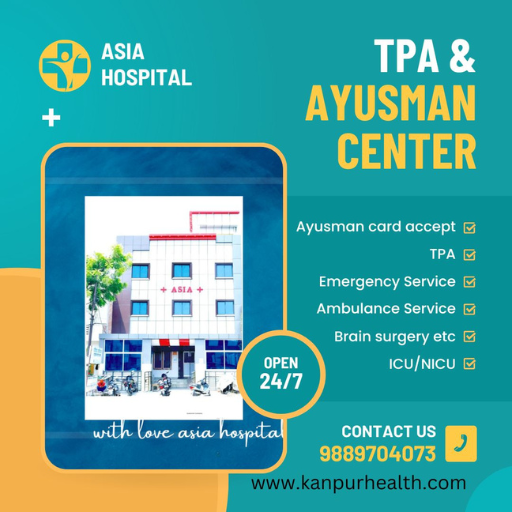

Your Health Is Our Priority - "Asia Hospital Kanpur"

Asia Hospital Kanpur provides exceptional healthcare services with state-of-the-art facilities and experienced medical professionals. We are committed to delivering compassionate care and improving the health and wellbeing of our community through innovative medical practices and personalized treatment plans.

Our Services

Wheather Our Services Are Cheap And Best Treatment But No compromise Of International Standard Of Treatment. Our Speciality Team Always Think About International Quality Of Treatment.

General medicine

General Surgery

Laproscopic Surgery

Neurosurgery

Gynecology

Urology

Gastrology

Pulmonology

Call For Bookings and Appointments

Book Your Doctor Appointment Instantly at Asia Hospital, Kanpur Enjoy hassle-free scheduling with our 24/7 appointment services.